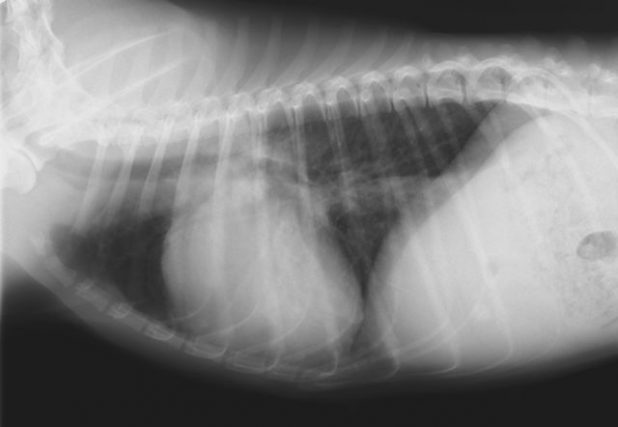

レントゲン検査

重度の右心拡大が認められたほか、肺炎を疑う所見が確認されました。